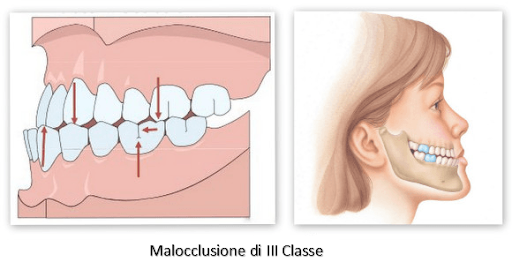

Per tonsillite acuta si intende comunemente l’infiammazione delle tonsille palatine, visibili nell’orofaringe, lateralmente all’ugola. A partire dalla prima infanzia, le tonsille palatine vanno incontro a una progressiva atrofia.